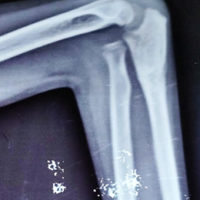

Radiographs (antero‑posterior views of both shoulders) confirmed bilateral anterior dislocations of the glenohumeral joints without associated fracture (Fig. 3).

Figure 3: Pre-reduction anteroposterior radiograph showing bilateral anterior dislocation of the humeral heads (right and left) projected anterior to the glenoid fossae with squaring of both shoulders (Epaulets Sign). There is no associated fracture.

The Light bulb sign was absent. Baseline blood investigations were normal and done to rule out hypoglycemia and dyselectrolytemia.